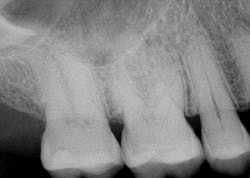

A healthy 55-year-old male presented with the chief complaint that his gum tissue on the upper right side had been hurting for the last few months. He thought something was stuck in the tissue and had unsuccessfully “tried to pick out whatever was stuck in there.” He pointed to the area around tooth No. 3.

A radiograph assessment revealed a slight radiolucency at the apex of the palatal root on tooth No. 3 (figure 8). Biting and percussion was WNL; probing depths were 6 mm interproximal and 3–4 mm on the facial/lingual. Cold and electric pulp tests were negative. The vestibular area in the No. 3–4 area was tender to palpation. Clinically, a large fracture line was noted on the lingual and on the distal marginal ridge (figure 9).

Diagnosis: Necrotic No. 3 with likely association of extended fracture line into the pulpal space. Recommendations were given to the patient, who opted for extraction and eventual implant placement. Upon removal of the tooth, the following was noted (figure 10):

- Lingual fracture line extending approximately 5 mm below the CEJ

- Existing restoration was removed and the crack line was observed to run across the pulpal floor in a mesiodistal fashion

- Wedging was done, and there was a noted flexuration in the cusps